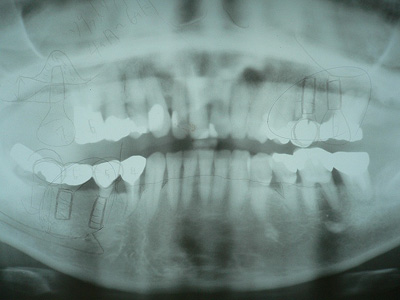

下顎右側5番に抜歯即時埋入をおこない、6番に通常埋入した症例

患者さん:50代女性

術前レントゲン写真

下顎右側AD67Gブリッジが動揺し、保存・再製が困難でした。

そのために抜歯して右下56部にインプラント治療を計画しました。